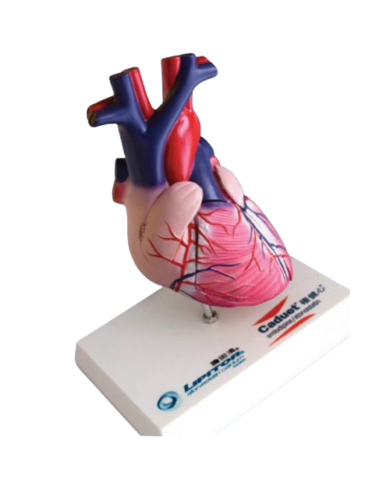

Modello anatomico PER FORNITURE CASE FARMACEUTICHE

Modello anatomico PER FORNITURE CASE FARMACEUTICHE

Modello anatomico PER FORNITURE CASE FARMACEUTICHE

Modello anatomico PER FORNITURE CASE FARMACEUTICHE

Modello anatomico PER FORNITURE CASE FARMACEUTICHE

Modello anatomico PER FORNITURE CASE FARMACEUTICHE

Modello anatomico PER FORNITURE CASE FARMACEUTICHE

Modello anatomico PER FORNITURE CASE FARMACEUTICHE

Modello anatomico PER FORNITURE CASE FARMACEUTICHE

Modello anatomico PER FORNITURE CASE FARMACEUTICHE

Modello anatomico PER FORNITURE CASE FARMACEUTICHE

Modello anatomico PER FORNITURE CASE FARMACEUTICHE

Modello anatomico PER FORNITURE CASE FARMACEUTICHE

Modello anatomico PER FORNITURE CASE FARMACEUTICHE

Modello anatomico PER FORNITURE CASE FARMACEUTICHE

Modello anatomico PER FORNITURE CASE FARMACEUTICHE

Modello anatomico PER FORNITURE CASE FARMACEUTICHE

Modello anatomico PER FORNITURE CASE FARMACEUTICHE

Modello anatomico PER FORNITURE CASE FARMACEUTICHE

Modello anatomico PER FORNITURE CASE FARMACEUTICHE

Modello anatomico PER FORNITURE CASE FARMACEUTICHE

Modello anatomico PER FORNITURE CASE FARMACEUTICHE